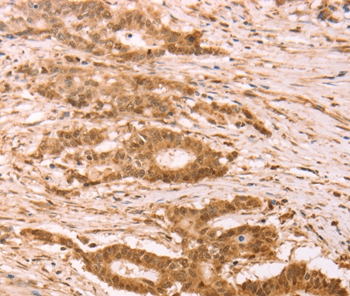

Immunohistochemical analysis of paraffin-embedded Human colon cancer tissue using #37262 at dilution 1/25.

Immunohistochemical analysis of paraffin-embedded Human lung cancer tissue using #37262 at dilution 1/25.